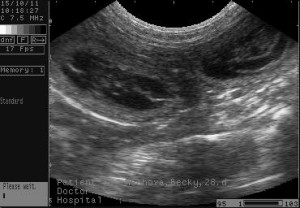

Na ultrazvuku jsou zřetelně vidět dvě štěňátka, třetí je trošku schované, ale s největší pravděpodobností si lebedí v Bekynce také!

Předpokládaný termín narození - 19.11.2011

....a zde je máme (28. den)....